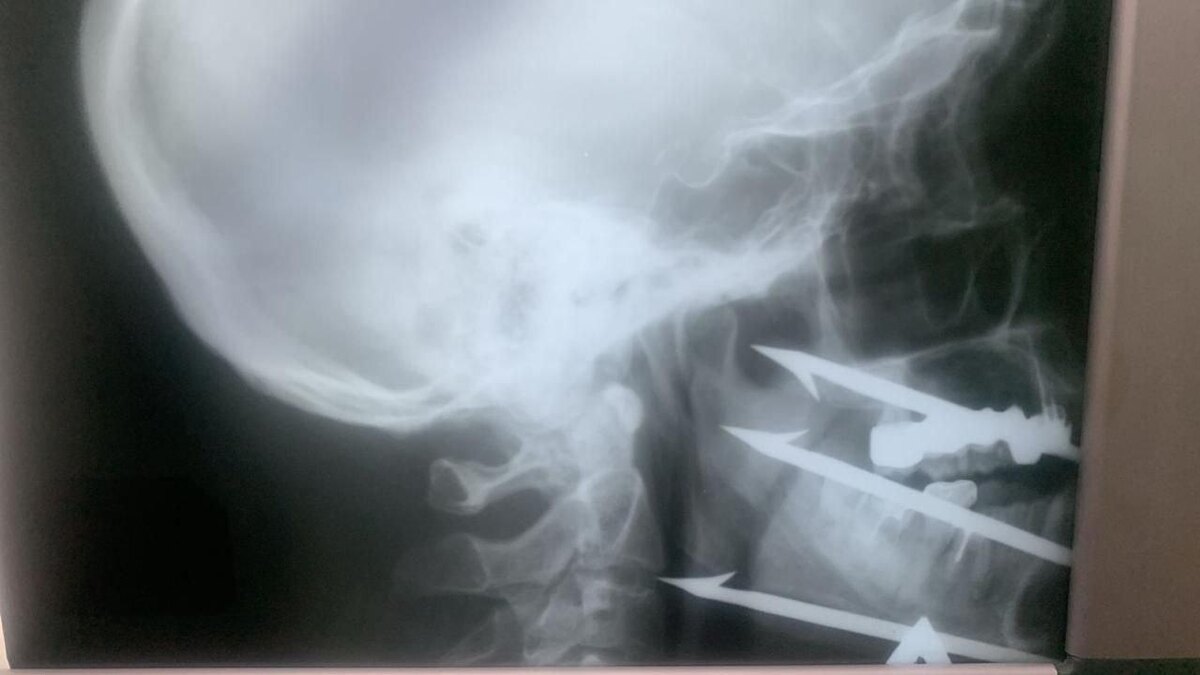

Хирурги спасли рыбака, выстрелившего в лицо из гарпуна Волгоградские врачи провели уникальную операцию, извлекая трёхзубый гарпун из лица 52-летнего рыбака. Инородное тело остановилось в миллиметре от сонной артерии, что делало любое неверное движение смертельно опасным. Операцию выполнила объединённая бригада хирургов из городских больниц. Сейчас жизнь пациента вне опасности, ему предстоит реабилитация. 🤩 Все самые заметные новости. Подписывайтесь!

Волгоградские врачи провели уникальную операцию, извлекая трёхзубый гарпун из лица 52-летнего рыбака. Инородное тело остановилось в миллиметре от сонной артерии, что делало любое неверное движение смертельно опасным. Операцию выполнила объединённая бригада хирургов из городских больниц. Сейчас жизнь пациента вне опасности, ему предстоит реабилитация.